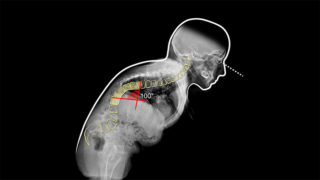

Rimosse due vertebre, raddrizzata schiena curva di 100 gradi: l’intervento senza precedenti a Bologna

Un intervento chirurgico pionieristico e senza precedenti è quello eseguito all’istituto ortopedico Rizzoli di Bologna dove a una paziente in sedia a rotelle sono state rimosse due vertebre toraciche non contigue per riportare dritta la sua colonna vertebrale. La donna soffriva di una gravissima cifosi che determinava una curva di oltre cento gradi, considerata inoperabile.

L’intervento invece è stato reso possibile grazie a una tecnica di ricostruzione in 3D, eseguita dall’equipe del prof. Cesare Faldini, direttore della Clinica ortopedica 1 dell’Istituto ortopedico Rizzoli, affiancato da anestesisti, rianimatori, neurofisiologi e infermieri. L’operazione è durata circa otto ore.

La paziente 54enne era andata incontro a una fusione patologica (anchilosi) di cinque vertebre toraciche. In piedi dopo sette giorni dall’intervento, ha iniziato il percorso di riabilitazione per camminare. La sua colonna vertebrale, incurvandosi in avanti, aveva determinato una cifosi che non le permetteva di stare in piedi.

A nulla erano valse le operazioni, e la deformità era considerata non più trattabile per gli elevati rischi di lesione del midollo spinale. La ricostruzione in 3D della colonna deformata è partita dalla Tac della paziente e ha permesso di pianificare la rimozione delle due vertebre e ‘guidare’ la correzione senza ledere il midollo spinale, con un movimento di correzione di oltre novanta gradi in un singolo intervento.

“Un risultato fino a oggi impensabile – spiega Faldini – ottenuto combinando la tradizione nella ricerca ortopedica, il Rizzoli compie in questi giorni 125 anni, con tecniche altamente innovative, per offrire una possibilità di correzione chirurgica a quelle rare scoliosi e cifosi fino a oggi considerate inoperabili per la loro gravità. Situazioni fortunatamente rare, ma gravemente menomanti per i pazienti: se la colonna si deforma oltre novanta gradi, cioè compie un angolo retto, da verticale diviene orizzontale, rendendo impossibile stare in piedi, e avere una vita di relazione accettabile”.